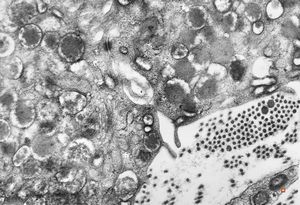

M,40y. | granular cell tumor

F,30y. | granular cell tumor